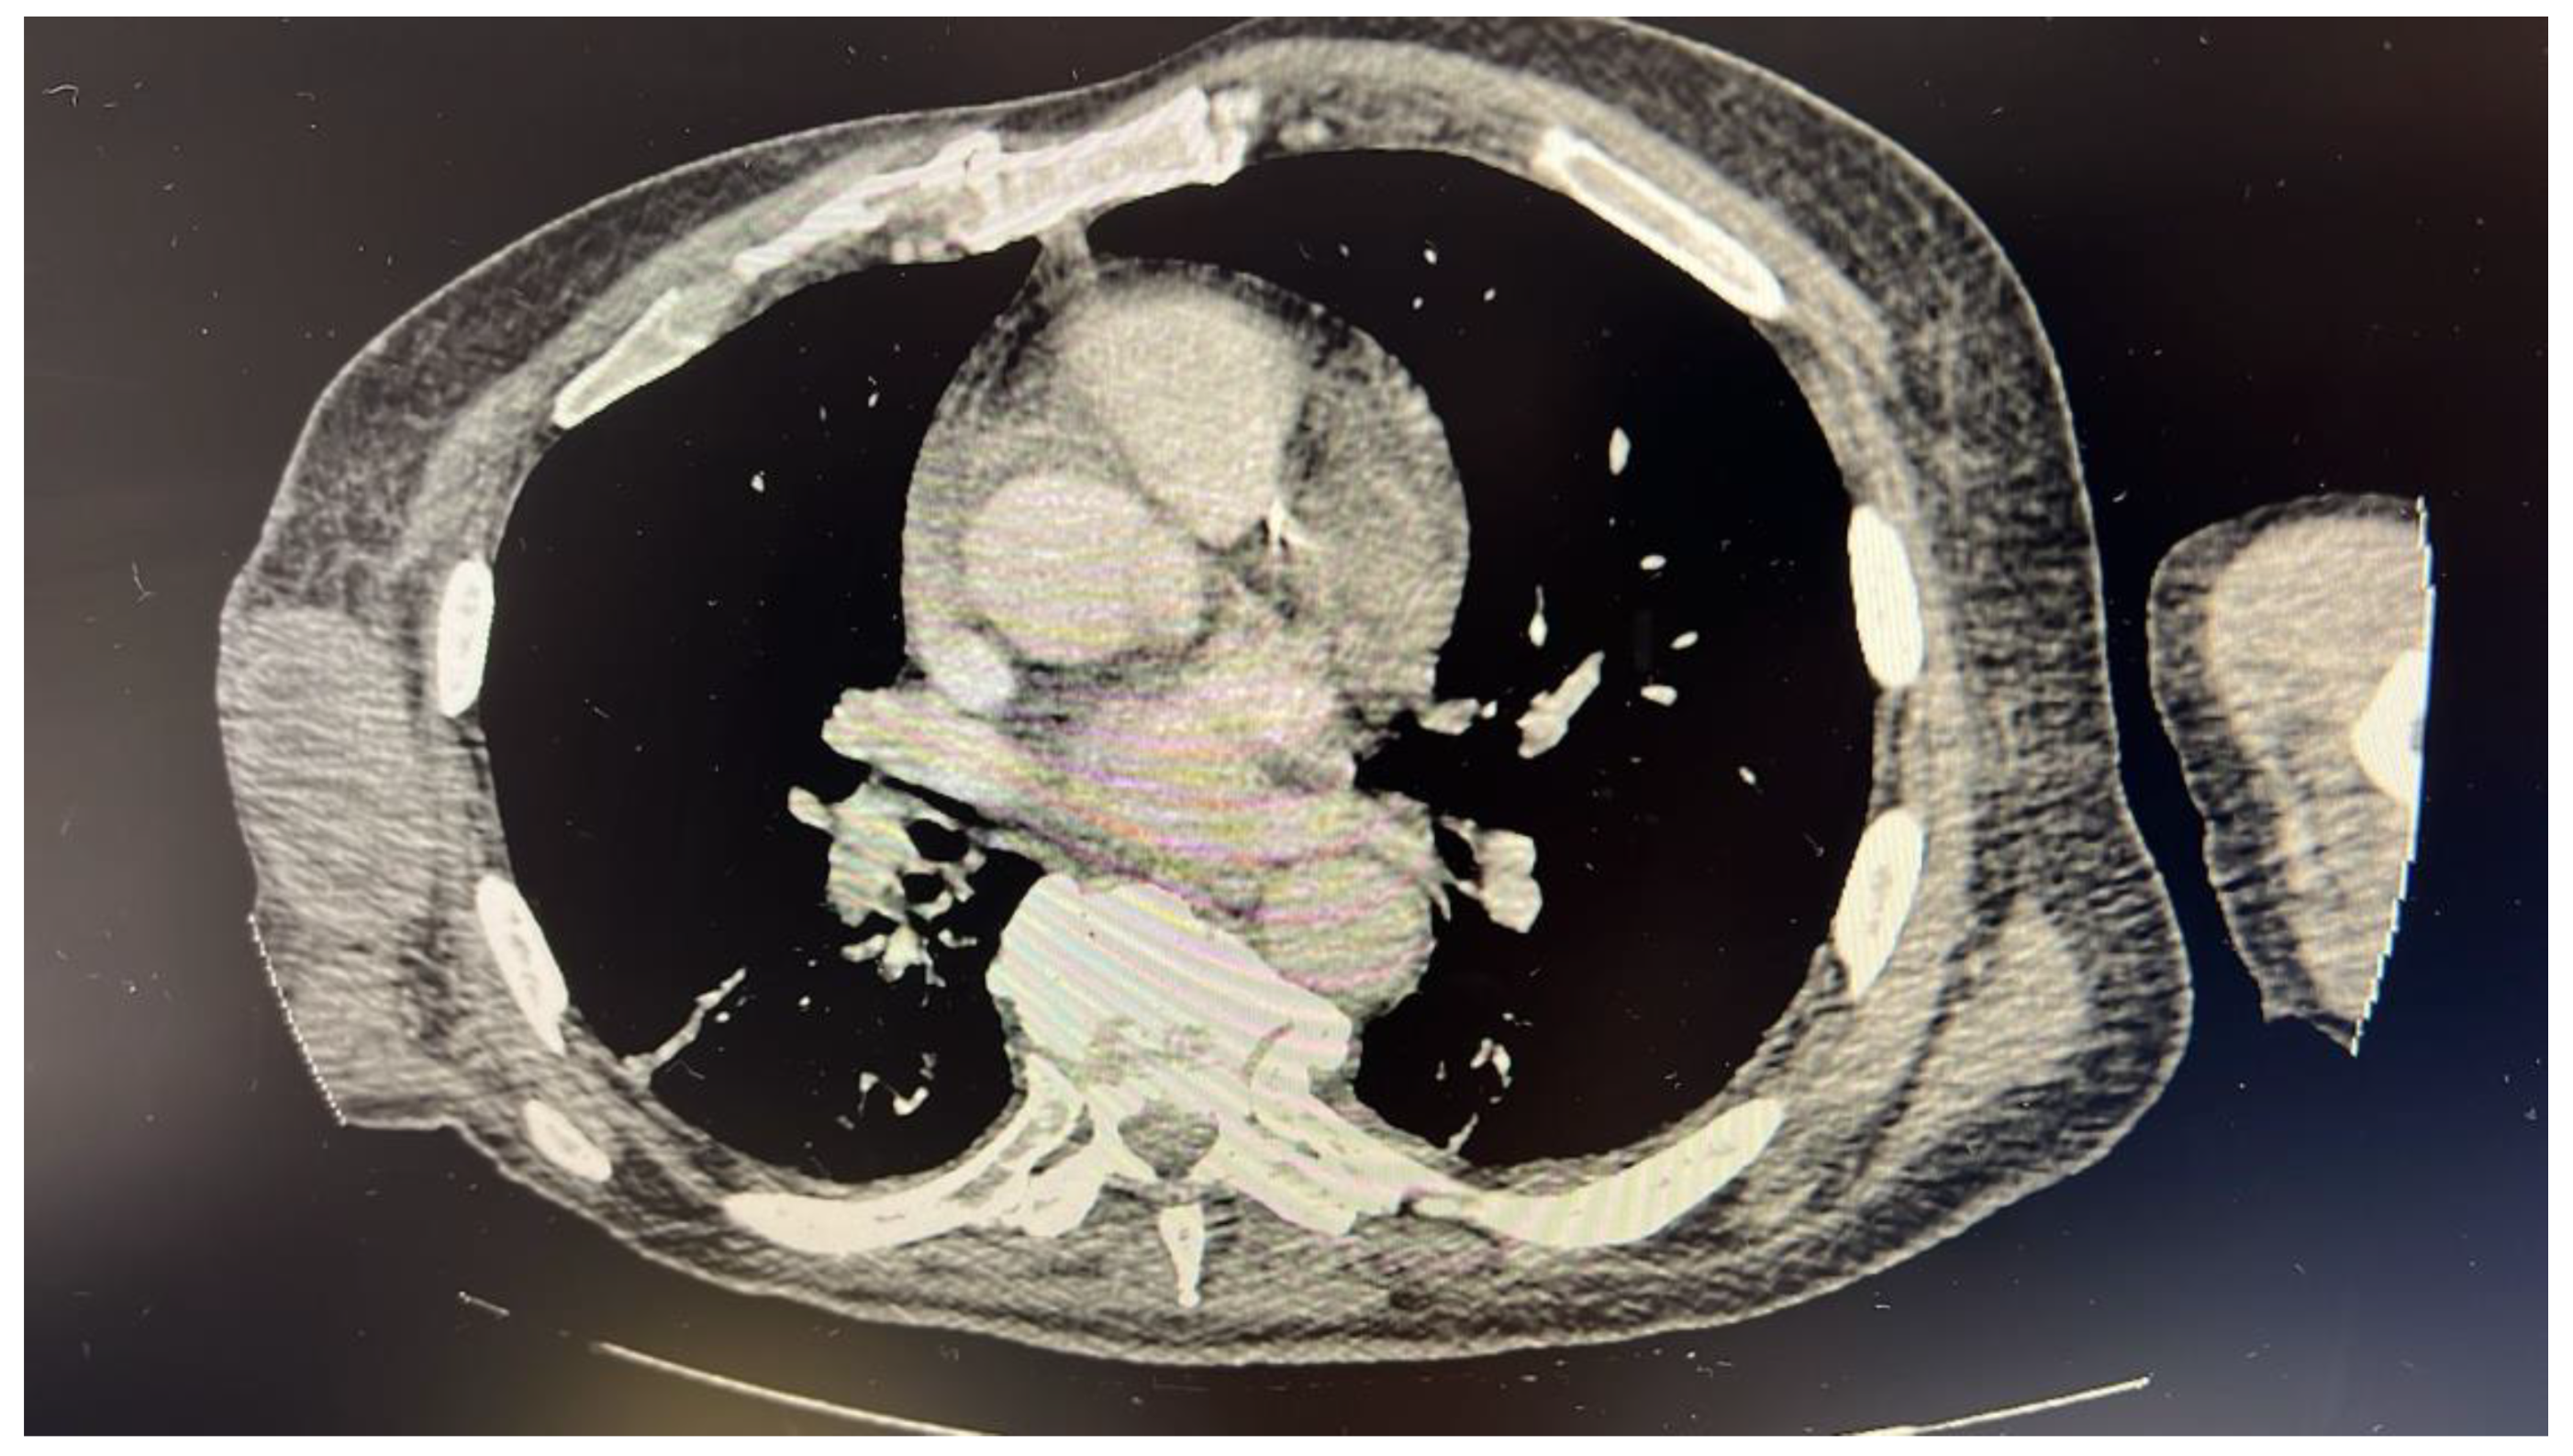

Upon arriving at the emergency department from urgent care, the patient displayed tachycardia (heart rate of 112), leukocytosis (43,000), thrombocythemia (841,000), anemia (hemoglobin 6.6), thrombophilia (1000), transaminitis, and an elevated troponin level (0.4). These findings may be seen in myeloproliferative neoplasms (thrombocythemia, myelofibrosis, and polycythemia vera) which cause the overproduction of blood cells. A computed tomography scan showed a right axillary soft tissue mass measuring 8.3 × 3.9 × 6.5 cm with multiple prominent retroperitoneal lymph nodes, suggestive of a neoplastic process (Figure 1).

Figure 1.

Computed tomography scan showing right axillary soft tissue mass measuring 8.3 × 3.9 × 6.5 cm with multiple prominent retroperitoneal lymph nodes.